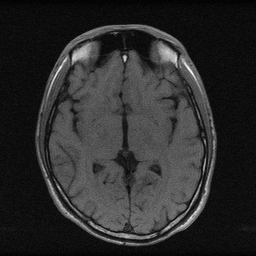

AI-powered reconstruction for portable and low-field MRI. Our models compensate for lower signal-to-noise ratios, delivering high-quality images.

Drag the slider to reveal how our AI reconstructs high-quality low-field images from undersampled k-space